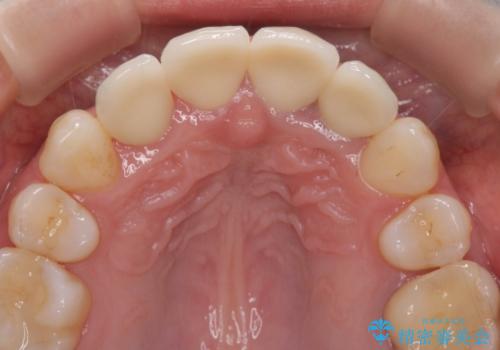

変色した歯を改善、セラミック治療

根管治療をしたのち時間が経過して変色が目立つ歯と、レジン充填が複数箇所に及んでいる歯も同時にオールセラミック治療を行っていくこととなりました。

- 52.8万円(ジルコニアクラウン×4・仮歯×4)費用は治療当時の料金となります

自然な歯の色に仕上げることができ、大変喜んでいただくことができました。